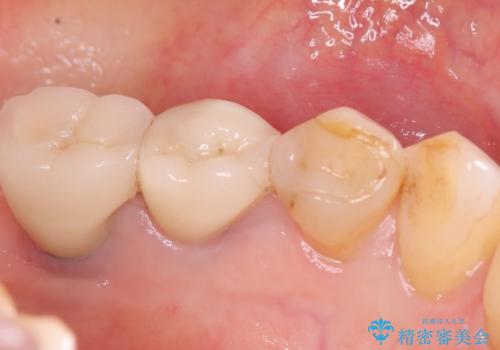

左下4番の歯頚部に知覚過敏症状を認めました。

5級窩洞のコンポジットレジン修復を過去に行ったおり、そのレジンも一部欠けてしまっている状態でした。

咬合力、食いしばりが強く他の歯にも知覚過敏症状が出ているような口腔内で、審美性良く劣化しない丈夫な修復を希望されたため、セラミッククラウンでの治療となりました。